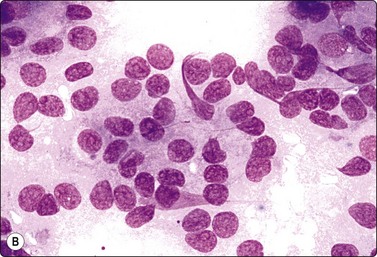

image image

Fig. 11.18 Islet cell tumor

(A) Poorly cohesive sheets and dispersal; cells with oval nuclei, stippled chromatin and small nucleoli (Pap, IP); (B) Mainly dispersed cells with uniformly round nuclei, speckled chromatin, moderate anisokaryosis; delicate cytoplasm; a suggestion of pseudorosettes (MGG, HP).

image

Fig. 11.19 Islet cell tumor

Tissue section corresponding to Figure 11.18 showing a trabecular and solid pattern (H&E, IP).

Criteria for diagnosis

Many single and loosely grouped cells, pseudorosettes,

Rounded monotonous nuclei, mild to moderate anisokaryosis,

Speckled chromatin and 1–3 small nucleoli,

Poorly defined, finely granular cytoplasm, often dispersed in the background,

Nuclei eccentric if cytoplasm intact.

These functional or nonfunctioning tumors of adults are situated mainly in the body and tail of the pancreas. The tumors are well within the scope of EUS cytodiagnosis.114,115 The neoplastic cells are mainly dissociated, but often form loose acinar or follicular clusters and curved or circular rows (Fig. 11.18). In the majority of cases, nuclei are characteristically round to oval and uniformly small. Occasionally, nuclear anisokaryosis may be prominent, but the nuclear chromatin pattern varies little between cells. The chromatin is evenly distributed, coarsely granular or ‘speckled’. The small nucleoli are not easily seen in Giemsa-stained smears. Due to its fragility, the cytoplasm is often dispersed in the background. When it is preserved, nuclei are eccentrically situated within defined cell borders. A very fine, red granularity is often discernible in MGG smears with high magnification. Clumps of amyloid may occasionally be seen, but necrosis is not observed.113,116-119 The cytological pattern of most islet cell tumors is sufficiently characteristic to be easily distinguished from that of pancreatic adenocarcinoma. Production and secretion of specific hormone products cannot be distinguished on the basis of routine cytological smears alone. If the secretory products of the neoplastic cells can be identified by immunocytochemical methods, a more specific diagnosis can be made with confidence. General neuroendocrine markers will usually be positive, such as neuron-specific enolase, synaptophysin, chromogranin-A, PGP9.5 and CD56. Specific secretory products, e.g. insulin can be marked by appropriate antibodies but this does not necessarily correlate with raised serum levels. Electron microscopy will demonstrate dense-core neurosecretory granules. A decision on whether a tumor is benign or malignant is problematic. Even histopathology is poorly predictive of aggressive behavior. In general, nuclear atypia and pleomorphism cannot be relied on as cytological criteria of malignancy (Fig. 11.20). More aggressive behavior correlates with a raised proliferation index assessed using Ki-67 immunohistochemistry (> 2%).120 This is a parameter in the WHO 2004 histology based-grading system.121,122 Only documentation of metastasis finally provides proof of malignancy.123,124